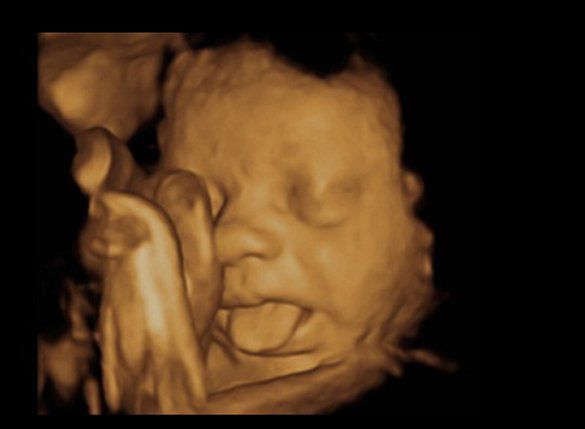

Động tác thè lưỡi đáng yêu này là của em bé nằm trong bụng mẹ Mick Jagger (Mỹ).